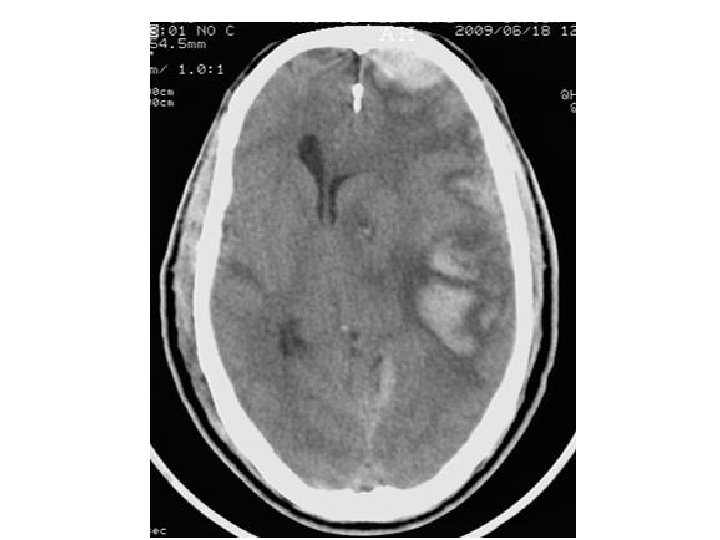

Les différentes lésions 2/2 • Hématome extra-dural – L'hématome extra-dural ou épidural est une accumulation de sang entre l'os du crâne et la dure-mère (enveloppe fibreuse du cerveau faisant partie des méninges). L'hématome extra-dural est une urgence chirurgicale absolue. Il se développe en quelques heures et peut entraîner la mort du patient par engagement cérébral si rien n'est fait. • Hématome sous-dural – Il s'agit d'un épanchement sanguin situé entre, en dehors la dure-mère, et en dedans l’arachnoïde. Il peut survenir de façon aiguë, au cours des heures suivant le traumatisme (hématome sous-dural aigu). Il est alors fréquemment associé à une contusion cérébrale dont peut dépendre le pronostic. Il peut aussi se constituer à bas bruit, et se démasquer quinze jours, voire des semaines après un traumatisme relativement peu important (hématome sous-dural chronique). • Hémorragie intracérébrale – Il s'agit d'un saignement à l'intérieur du parenchyme cérébral. • Hémorragie méningée – Une hémorragie méningée est observée dans 1/3 des traumatismes crâniens sévères. Elle peut être secondaire à la lésion d'un vaisseau méningé, ou bien à une suffusion hémorragique à partir d’un foyer de contusion du cortex cérébral.